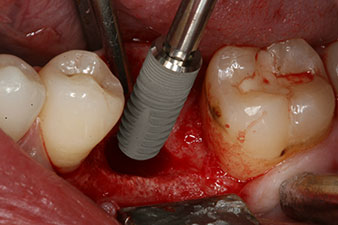

Фиг. 2: Шест седмици по-късно в областта на корена мезиално има непълно осифицирана алвеола.

Шест седмици след екстракцията се открива непълна осификация след препарацията на мукопериосталното ламбо в областта на предходната алвеола мезиално.